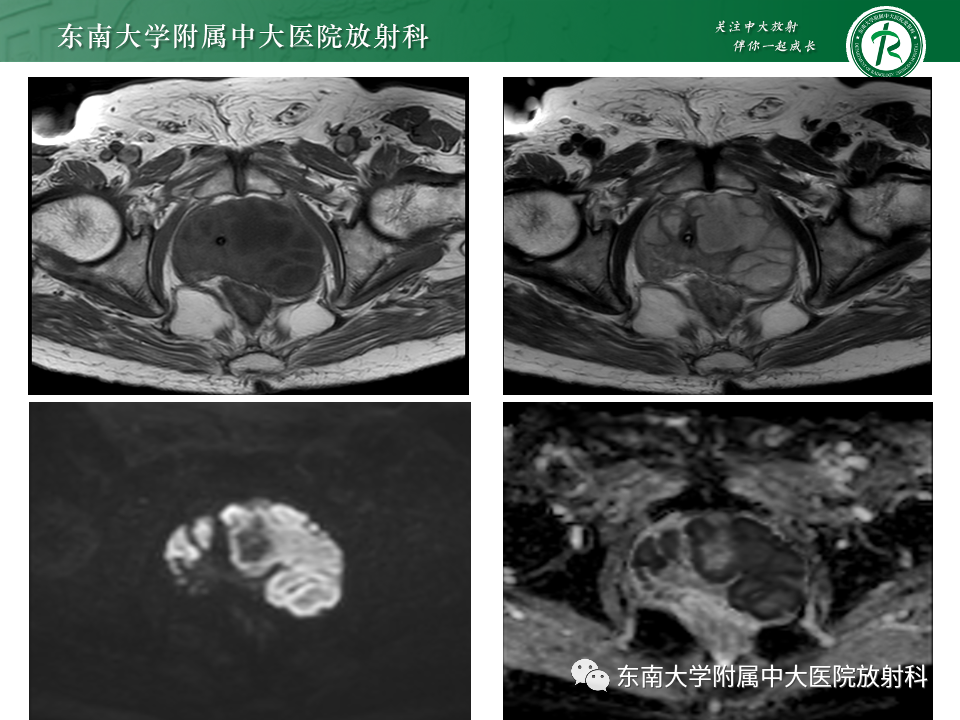

病史

男,68岁,发烧伴肛周疼痛1月

既往史:10月前于外院行“直肠癌根治术”,病理为中分化腺癌

B超提示:前列腺左侧叶低回声团,占位?